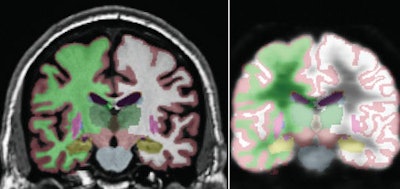

![]() |

| Automated segmentation in a 71-year-old healthy male. MR image (left) segmentation is compared to segmentation of coregistered FDG-PET volume (right), with regions of interest including the hippocampus (gold), thalamus (dark green), caudate (blue), putamen (pink), and lateral ventricle (purple). The right and left hemisphere white matter (green and white, respectively) and gray matter (maroon) also are shown. Image courtesy of Radiology. |